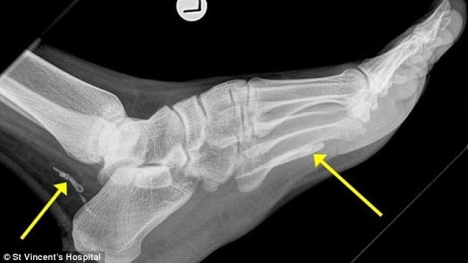

Hãi hùng phát hiện giun chỉ dài 1 mét sống trong chân ít nhất 4 năm

Người đàn ông Sudan 38 tuổi này hiện đang sống ở Melbourne, Australia đã được các bác sĩ bệnh viện St Vincent, Sydney phát hiện ra con giun chỉ dài 1 mét đã chết và đang bị phân hủy ở trong mắt cá chân nhờ chụp X-quang.